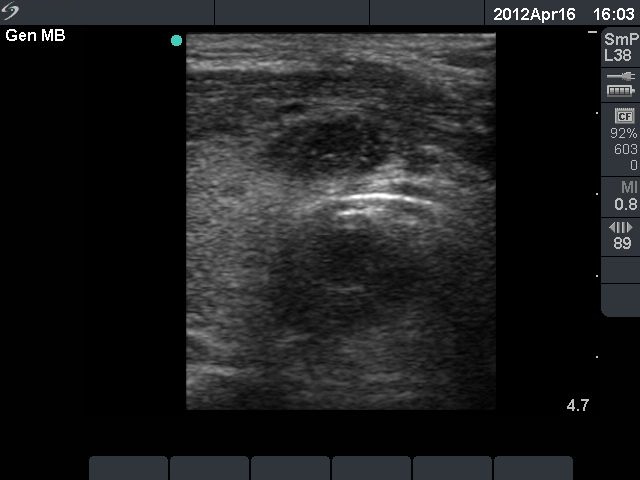

Second row: ultrasonographic picture before the second sclerotherapy. The size of the lesion was 38x28x39 mm (width x depth x length).